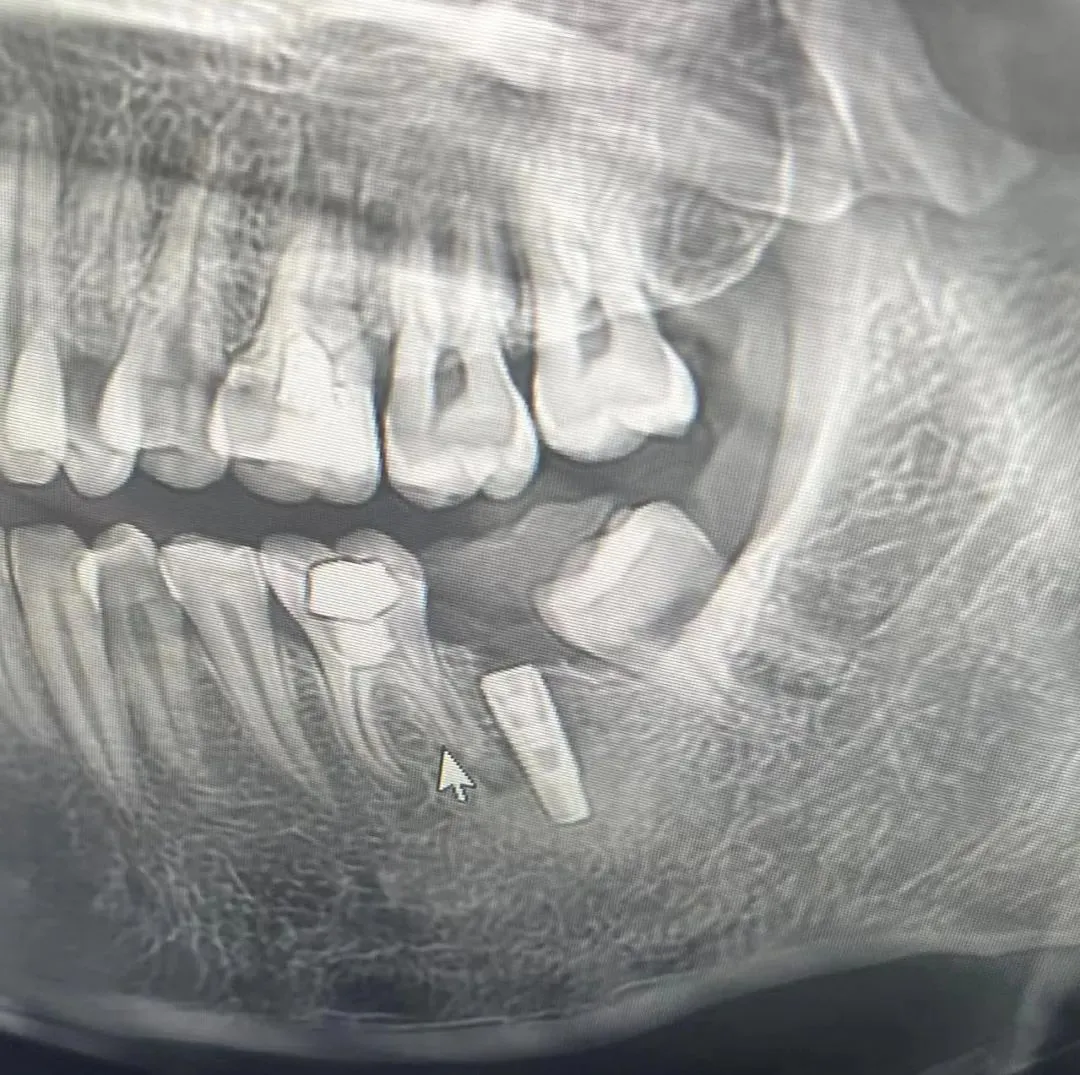

7、种植影像学分析;可以获得骨高度 ,骨宽度信息 ,甚至可以模拟种植体植入位点

11、精准种植;单颗前、后牙的理想植入位点

六、学员回家后部分病例